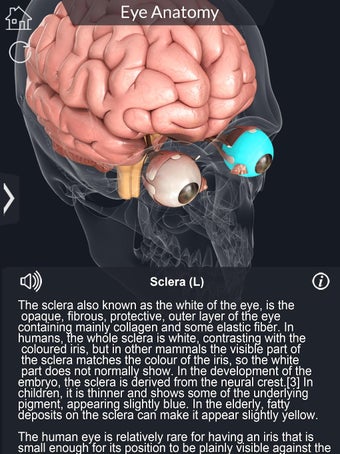

Каждая часть разделена на отдельный вид, где вы можете можно увидеть название детали и ее расположение на глаз.